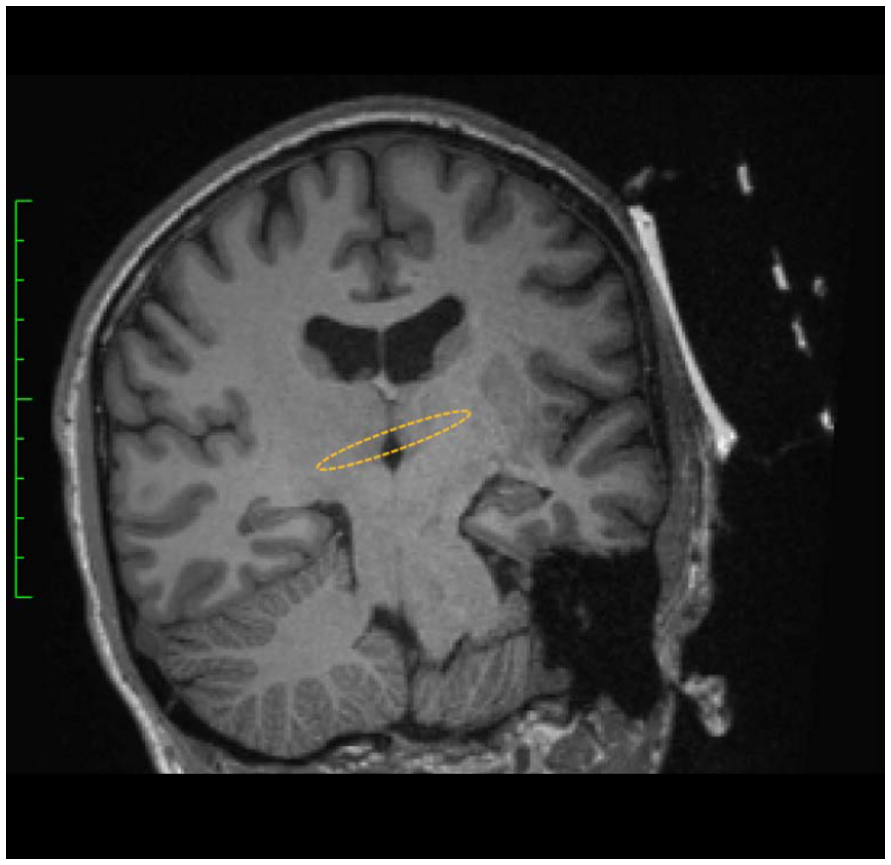

Soterix Medical tFUS + Localite

Soterix Medical 的 BrainSonix tFUS 系統可與 Localite 導航系統結合,提供無縫的導航體驗。